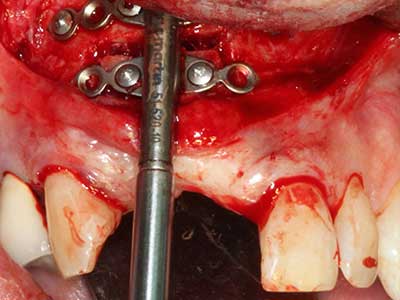

Indication: Preparation near nerves

As noted above, indications for piezo surgery can also be found in the field of conservative dental surgery. Special working tips simplify the exposure of root tips and make it easier to protect nerves and sinus mucous membranes, particularly in the lower premolar and upper posterior tooth regions. Angled diamond tips are used to precisely prepare the resection cavity for the retrograde root filler material for unsealed apical obturation. The ultrasonic technology means the tips can be very slender, which improves the view and the size of the access cavity. As a result, the application of ultrasonic surgery for this indication is one of the standard procedures for apical resection (Del Fabbro, Tsesis et al. 2010, Scarano, Artese et al. 2012).

Indication: Apical resection

When surgical procedures are performed on bone in the immediate vicinity of sensitive structures such as blood vessels or nerves, rotary instruments pose a significant risk of iatrogenic injury. Piezoelectric devices can be helpful for preparation of bone covers and removal of hard tissue close to nerves, particularly for exposure of nerves after iatrogenic injury but also during nerve lateralization for resective and reconstructive procedures or implant placement (Fig. 17-20). Light contact between the piezotip and the nerve does not generally result in damage but proceeding incautiously with saw-like motions or attachments where a residual bone substrate remains may cause temporary or even permanent nerve damage. However, the risk of damage is considered to be substantially lower than when using saws or milling instruments (Pereira, Gealh et al. 2014).